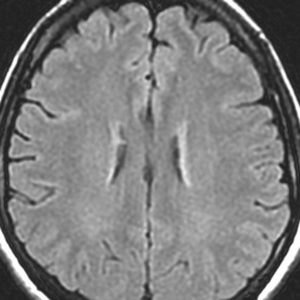

左前頭葉のグリオーマ oligodendroglioma に54グレイ27分割の放射線治療が行われました。治療直後のフレア画像(左)では深部白質に異常信号はありません。

2年後のフレア画像です

側脳室壁と深部白質 (半卵円中心) にびまん性の高信号が出現しています

無症状です

グリオーマが再発したのではないかと思ってしまいますが違います